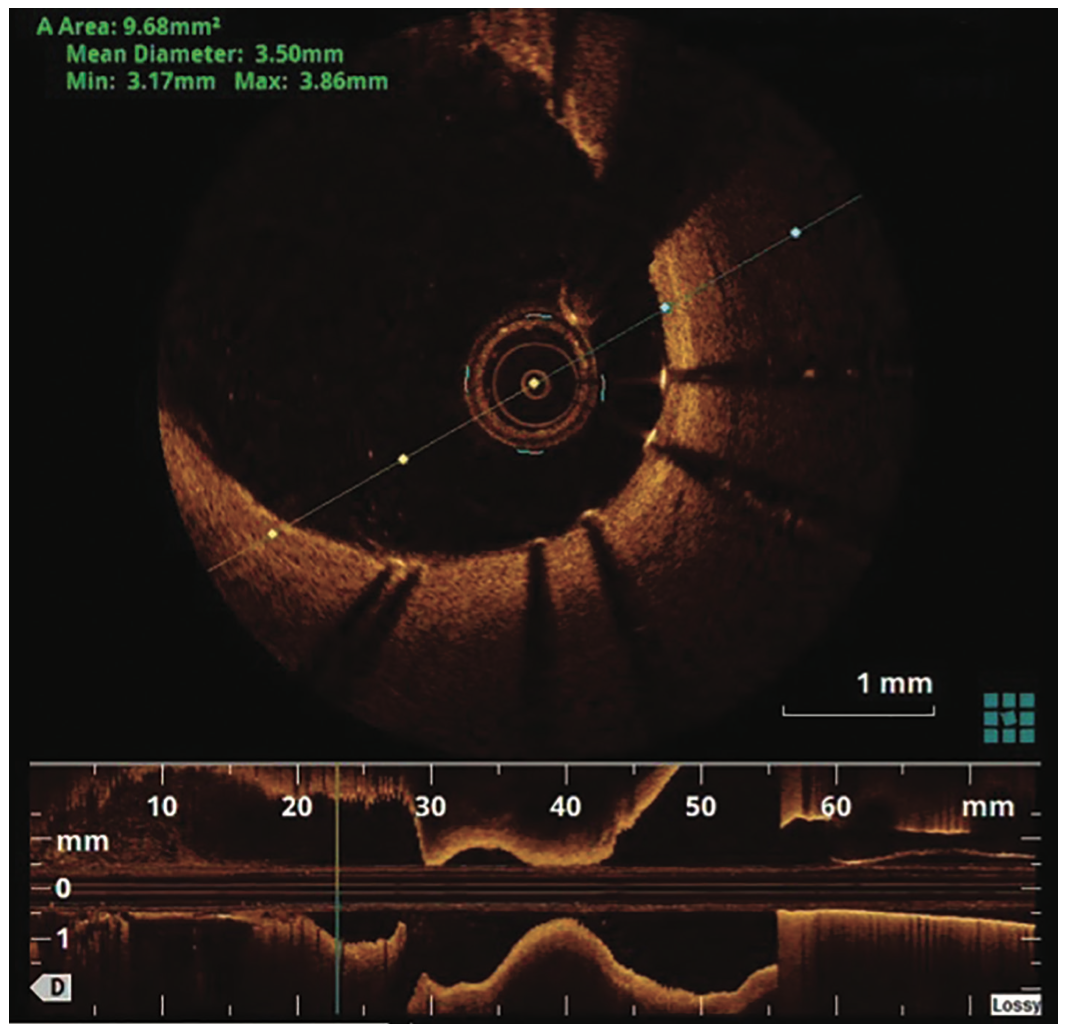

A 69-year-old woman with history of hypertension, paroxysmal atrial fibrillation, coronary artery disease, non-insulin dependent type II diabetes and hyperlipidemia presented with one-week history of chest tightness associated with worsening dyspnea on exertion. She had previously presented with non-ST segment elevation myocardial infarction 6 months earlier, requiring placement of a single 4 x 24 mm Synergy DES (Boston Scientific) in the mid LAD (Figure 1) and subsequent OCT imaging (Abbott) demonstrating adequate stent expansion and apposition (Figure 2). Electrocardiogram on current presentation revealed T wave changes in anterolateral leads and cardiac biomarkers were noted to be significantly elevated.

Coronary angiography, via right radial artery access, revealed a large LAD with a patent mid stent with native coronary ectasia and saccular aneurysm formation around the stented segment (Figure 3). The remainder of the coronaries were unremarkable. A 6 French XB 3.0 guide (Medtronic) was used to selectively engage the left main coronary artery. A Samurai guidewire (Boston Scientific) was advanced across the LAD stent into the apical segment. OCT imaging of the mid LAD confirmed adequate apposition of the stent at the distal and proximal segments, with significant ectasia and malapposition in the aneurysmal mid segment of the vessel around the stent (Figure 4). No further intervention was performed at that setting. These findings were discussed with the patient and the primary team, along with cardiothoracic surgery, upon patient recovery. Treatment options, specifically surgical ligation of the LAD with coronary artery bypass grafting to the LAD and diagonal branches, a percutaneous approach with covered stent placement in the mid LAD to exclude the aneurysm, and a conservative medical therapy approach were deliberated. The patient firmly refused surgical intervention after understanding the risks and benefits of all the treatment options offered to her. Conservative medical therapy was deemed inappropriate in this setting of myocardial infarction.